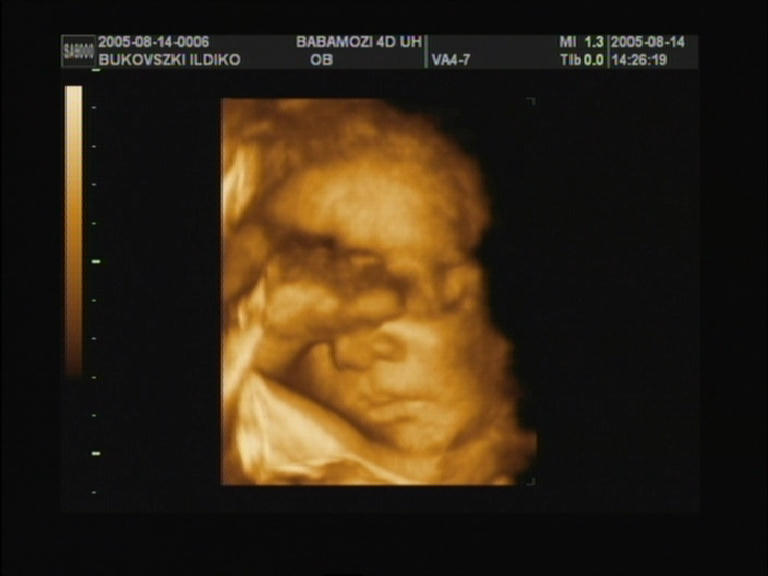

elkészült végre a 4D-s ultrahang is... ez lett a legjobb

kép... 30. hét |

30.hét..egy kis mosollyal |

![]() |